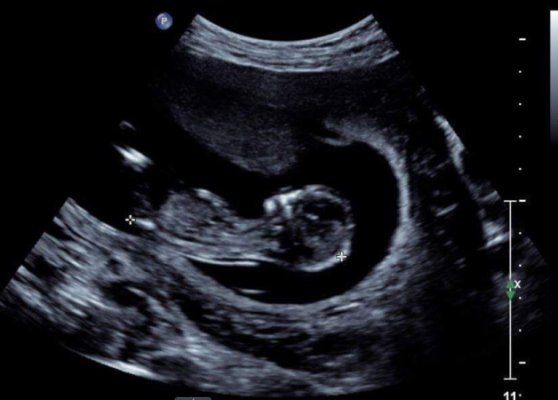

I posted this on the strictly nub theory page on fb and the moderator guessed boy. I was so desperate for a girl. Does it look like a boy nub? This is my last baby so I need to start getting my head around it now I think. Scan was at 13weeks (baby measured 12weeks 6 days at this scan).

Thanks Attachment 41811Attachment 41812